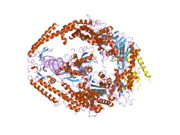

Hereditary nonpolyposis colorectal cancer (HNPCC), sometimes referred to as Lynch syndrome, is inherited in an autosomal dominant fashion, where inheritance of only one copy of a mutated mismatch repair gene is enough to cause disease phenotype. Mutations in the MSH2 gene account for 40% of genetic alterations associated with this disease and is the leading cause, together with MLH1 mutations.[9] Mutations associated with HNPCC are broadly distributed in all domains of MSH2, and hypothetical functions of these mutations based on the crystal structure of the MutSα include protein–protein interactions, stability, allosteric regulation, MSH2-MSH6 interface, and DNA binding.[10] Mutations in MSH2 and other mismatch repair genes cause DNA damage to go unrepaired, resulting in an increase in mutation frequency. These mutations build up over a person's life that otherwise would not have occurred had the DNA been repaired properly.

In eukaryotes from yeast to humans, MSH2 dimerizes with MSH6 to form the MutSα complex,[13] which is involved in base mismatch repair and short insertion/deletion loops.[14] MSH2 heterodimerization stabilizes MSH6, which is not stable because of its N-terminal disordered domain. Conversely, MSH2 does not have a nuclear localization sequence (NLS), so it is believed that MSH2 and MSH6 dimerize in the cytoplasm and then are imported into the nucleus together.[15] In the MutSα dimer, MSH6 interacts with the DNA for mismatch recognition while MSH2 provides the stability that MSH6 requires. MSH2 can be imported into the nucleus without dimerizing to MSH6, in this case, MSH2 is probably dimerized to MSH3 to form MutSβ.[16] MSH2 has two interacting domains with MSH6 in the MutSα heterodimer, a DNA interacting domain, and an ATPase domain.[17]

The MutSα dimer scans double stranded DNA in the nucleus, looking for mismatched bases. When the complex finds one, it repairs the mutation in an ATP dependent manner. The MSH2 domain of MutSα prefers ADP to ATP, with the MSH6 domain preferring the opposite. Studies have indicated that MutSα only scans DNA with the MSH2 domain harboring ADP, while the MSH6 domain can contain either ADP or ATP.[18] MutSα then associates with MLH1 to repair the damaged DNA.

MutSβ is formed when MSH2 complexes with MSH3 instead of MSH6. This dimer repairs longer insertion/deletion loops than MutSα.[19] Because of the nature of the mutations that this complex repairs, this is probably the state of MSH2 that causes the microsatellite instability phenotype. Large DNA insertions and deletions intrinsically bend the DNA double helix. The MSH2/MSH3 dimer can recognize this topology and initiate repair. The mechanism by which it recognizes mutations is different as well, because it separates the two DNA strands, which MutSα does not.[20]